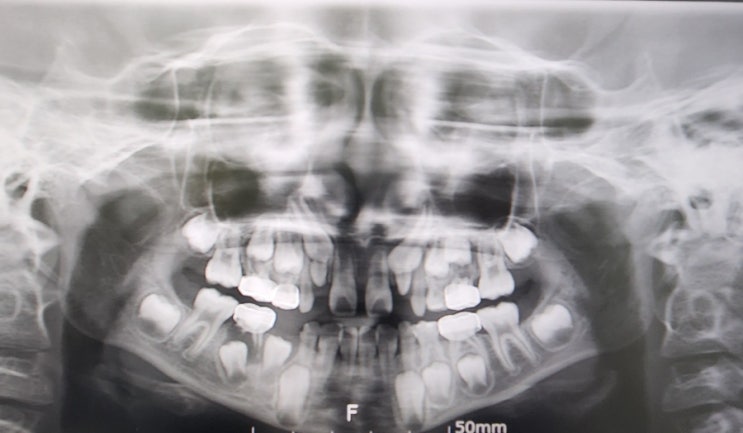

부산대치과병원 영구치 발치

영구치 발치를 했어요. 유치도 아니고 이게 맞나 싶었지만 뒀다가는 멀쩡한 송곳니도 못 날 수 있다기에 발...